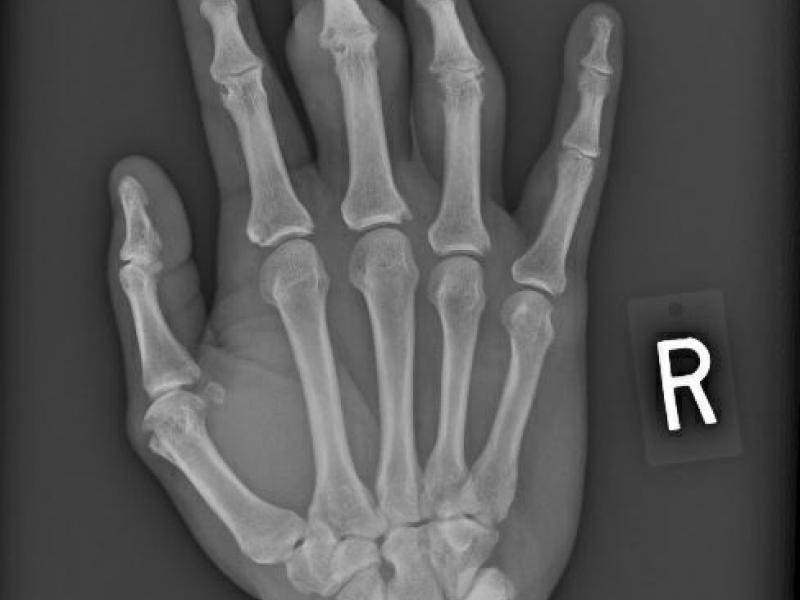

History 50 yo male with hx of gout on intermittent